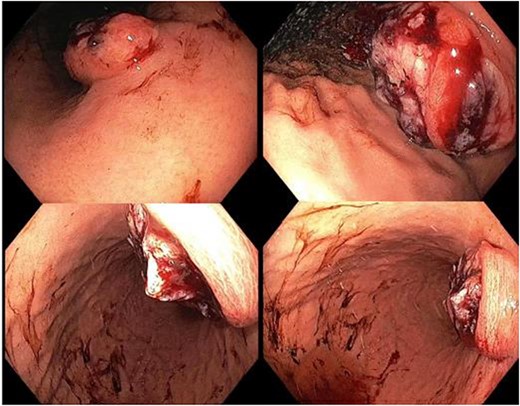

A 65-year-old female was referred to the general surgical outpatient clinic with a 6-month history of epigastric pain and dyspepsia. The patient’s only other medical history was eczema. Physical examination revealed a soft abdomen with no palpable mass. A 10 cm fungating, malignant appearing mass was identified along the gastric lesser curvature on upper gastrointestinal endoscopy (Fig. 1). Histopathology of the biopsied mass demonstrated spindled and small round blue cell tumor with immunohistochemistry staining consistent with Ewing-like sarcoma. Computed tomography (CT) of the abdomen and pelvis showed an enhancing nodular lesion with central calcification and an indeterminate 4 mm lymph node along the lesser curvature of the stomach which raised concerns for gastric malignancy (Fig. 2). Intense fluorodeoxyglucose (FDG) uptake was noted along the lesser curvature of the stomach on staging positron emission tomography (PET) (Fig. 3). There was no evidence of distant metastasis.

Upper gastrointestinal endoscopy showing a fungating, malignant appearing tumor along the gastric lesser curvature.